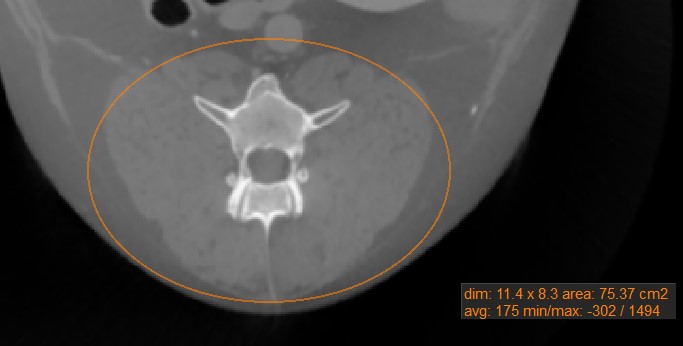

Oval¶

Wählen Sie das Werkzeug Oval

aus und weisen Sie es einer der verfügbaren Maustasten zu. Starten Sie die Messung, indem Sie auf die aktive Bildschicht klicken und die Maus ziehen, um eine ovale Form zu erstellen. Lassen Sie die Maus los, wenn die Größe des markierten Bereichs zufriedenstellend ist.

Alle verfügbaren Messwerte werden zusammen mit der Messung angezeigt.

Ändern Sie den markierten Bereich, indem Sie einen der vier Punkte des um das Oval gezeichneten Rechtecks mit dem Werkzeug Standard

verschieben.

Einige Messwerkzeuge im CT-Viewer werden verwendet, um einen Bereich auf der aktiven Bildschicht zu markieren. Es gibt vier Werte, die automatisch berechnet und zusammen mit diesen Messungen angezeigt werden.

Dim: Abmessungen der Messung (Breite, Höhe, Abstand)

Fläche: Die mit der Messung eingeschlossene Fläche, berechnet in Quadratzentimetern

Mittelwert: Der durchschnittliche Gewebedichtewert (HU), der durch die Messung erfasst wird. Höhere HU-Werte weisen auf dichteres Gewebe hin, wie z. B. Knochen.

Minimum/Maximum: Der Minimal- und Maximalwert geben den kleinsten und größten Gewebedichtewert an, der durch die Messung erfasst wird.